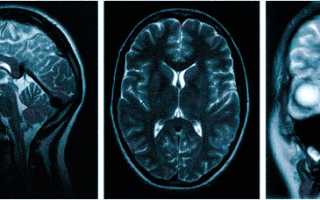

Множественные ишемические очаги при сосудистой деменции на МРТ: отсутствие памяти на недавние события и неадекватное поведение не являются признаками старости, своевременная диагностика деменции и патогенетическая терапия помогут замедлить прогрессирование болезни

МРТ — обследование, которое проводят не только при головной боли. Магнитно-резонансная томография поможет установить причины следующих жалоб: